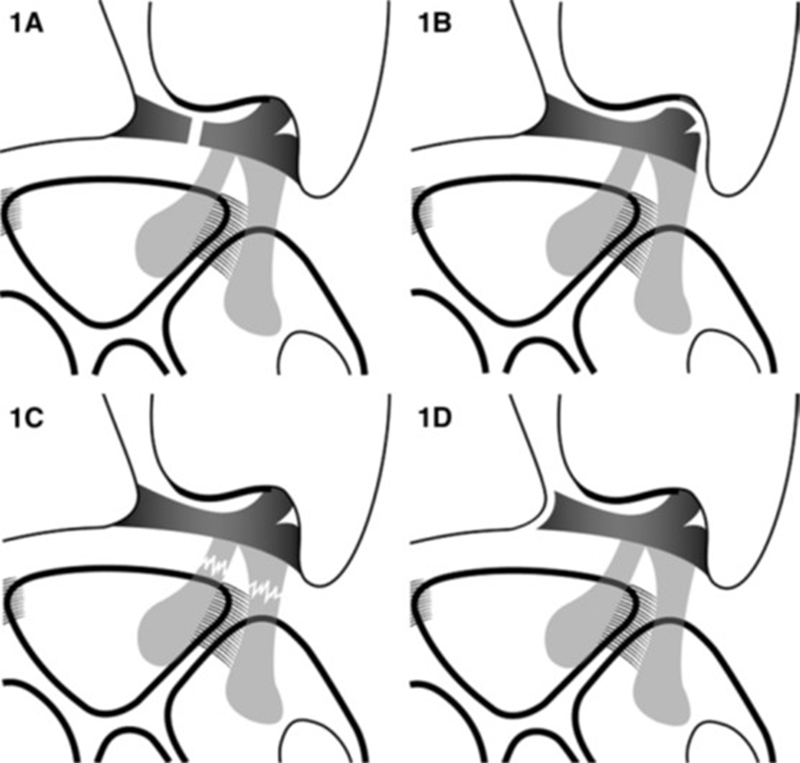

TFCC损伤分类(Palmer分类)

Ⅰ类:创伤性损伤

A:中心穿孔

B:尺侧撕裂(伴尺骨茎突骨折/不伴尺骨茎突骨折)

C:远端撕裂

D:桡侧撕裂

多发生在手腕过度伸展加上扭转的动作下,在远端尺骨处的手腕尺侧(小拇指侧)遭受外力的冲击。

Ⅱ类:退变性损伤

A:TFC磨损

B:TFC磨损+月/尺骨头软骨软化

C:TFC穿孔+月/尺骨头软骨软化

D:TFC穿孔+月/尺骨头软骨软化+月三角韧带撕裂

E:TFC穿孔+月/尺骨头软骨软化+月三角韧带撕裂+尺腕关节炎